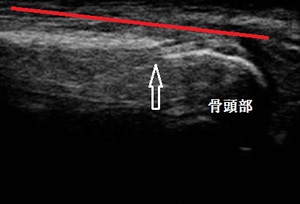

左踵(健側) 右踵 超音波長軸像 同部5週後

歩行時に踵を突いて歩くと激痛が起こります。超音波検査の結果、右踵の成長軟骨部に剥離した不正像が

認められました(上画像の丸の囲み)。

5週後の超音波検査の結果、初診時に剥離していた軟骨が骨癒合してほとんど左右差が無くなりました。